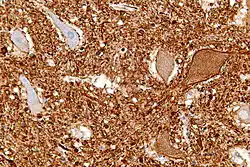

Central chromatolysis

Central chromatolysis is a histopathologic change seen in the cell body of a neuron, where the chromatin and cell nucleus are pushed to the cell periphery, in response to axonal injury.[1][2] This response is associated with increased protein synthesis to accommodate for axonal sprouting. In addition to traumatic injuries, central chromatolysis may be caused by vitamin deficiency (pellagra[3]).